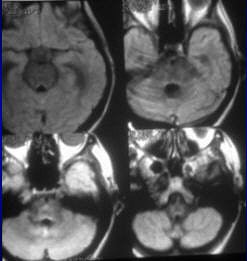

![]() |

| Seventy-eight-year-old female patient evaluated for suspected NPH. A and B, MRI FLAIR sequence (1 tesla, TR 11,000 msec, TE 140 msec, TI 2,600 msec) shows dilatation of the ventricles and sylvian fissures. C and D, FLAIR after 100% O2 for five minutes shows increased SI in the sulci and the posterior aspects of both sylvian fissures, allowing visualization of hypointense cysts (arrows) due to neurocysticerosis more anteriorly within the sylvian fissures. Note that there is no increase in the SI of the CSF within the ventricles. Braga FT, da Rocha AJ, Filho GH, Arikawa RK, Ribeiro IM, and Fonseca RB, "Intensity of CSF Depicted by Fluid-Attenuated Inversion Recovery Imaging," (AJNR, 24:1863-1868, October 2003). |